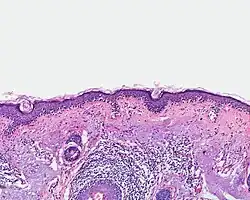

Lentigo-maligna-Melanom

Auf sonnengeschädigter Haut entstehen maligne Melanome in der Regel auf dem Boden eines zunächst auf die Epidermis begrenzten Melanoma in situ, der Lentigo maligna. Sie besteht in einer überwiegend einzelzelligen Ausbreitung atypischer Melanozyten entlang der Junktionszone und von Adnexstrukturen (Hautanhangsgebilden) vor dem Hintergrund einer atrophen (verschmälerten) Epidermis und elastotischen (sonnengeschädigten) Dermis. Mit dem Übergang in ein invasiv wachsendes Melanom spricht man vom Lentigo-maligna-Melanom. Die dermale Komponente weist entsprechend ihrem überwiegend horizontalen Wachstum eine geringe Eindringtiefe auf.

Die Melanozyten in der Lentigo maligna ebenso wie im Lentigo-maligna-Melanom sind zumeist klein und haben hyperchromatische (überstark angefärbte), abgewinkelt erscheinende Zellkerne. Der Pigmentierungsgrad des Zytoplasmas kann sich innerhalb einer Läsion stark unterscheiden.

Ebenfalls häufig finden sich Melanozyten mit auffälligen Dendriten (Zytoplasmaausläufern), insbesondere bei hellhäutigen Patienten. Dabei gelten eine Ausdehnung der Dendriten bis in das mittlere Stratum spinosum und eine deutliche Anisodendrozytose (Breitenvarianz der Dendriten) als Hinweis auf Bösartigkeit.[42]

Häufiger als in anderen invasiv wachsenden Melanomen zeigt sich im Lentigo-maligna-Melanom ein spindelzelliges Zellbild der dermalen Komponente. Die Tumorzellen breiten sich einzeln oder in teilweise auch strangförmigen Verbänden in der oberen Dermis aus. Diese weist eine desmoplastische Reaktion (tumorinduzierte Bindegewebsbildung) und ein an Lymphozyten und Melanophagen reiches Entzündungsinfiltrat auf.[43]

- Lentigo maligna (Melanoma in situ)

-

Einzelzellig und in Nestern verteilte Melanozyten entlang der Junktionszone (Übersicht) -

Einzelzellig und in Nestern verteilte Melanozyten entlang der Junktionszone. (Detail)